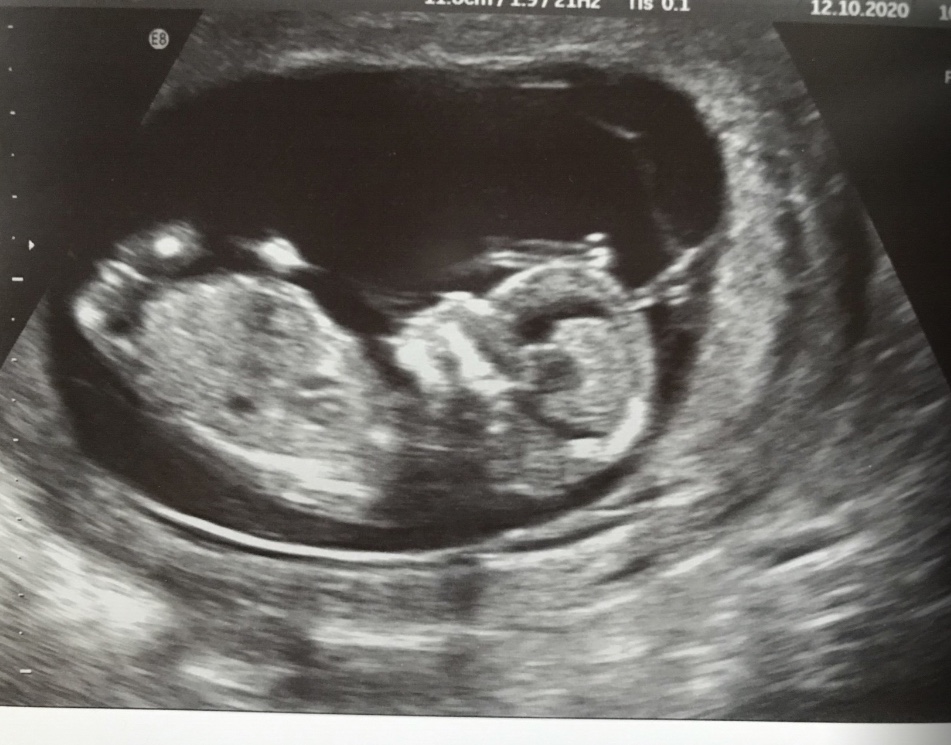

Ok, enough venting! Here are my scan pics from 13weeks.

Attachment 42925Attachment 42926Attachment 42927